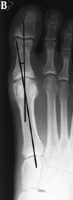

Hallux Valgus Angle

The hallux valgus angle (HAV) or hallux abductus angle is the angle formed between the longitudinal axis of the first proximal phalanx and the longitudinal axis of the first metatarsus.

Hallux VarusA.  In hallux varus or adductus the HAV is less then 5º. Normal Hallux Valgus Angle B. In normal subjects  HAV is 5º to 15º . Hallux abducto valgus is mild when HAV is 16º to 25º,Moderate Hallux Valgus C. moderate  when HAV is 26º to 35º, and severe Severe Hallux Valgus(D) when HAV is greater than 35º.